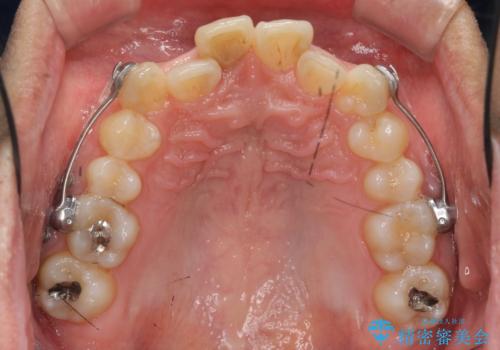

以上のような歯並びの問題をマウスピース矯正インビザライン・カリエール・マイクロインプラント・部分ワイヤー矯正

を用いて改善していきます。

深い噛み合わせと上顎前突の状態を治すのに時間がかかりましたが、治療後は理想的で安定した咬合関係となりました。